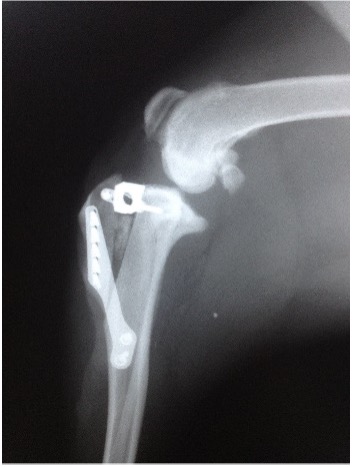

Q: What Is the TTA Procedure?

A: Tibial Tuberosity Advancement (TTA) is a surgical procedure used to stabilize the knee after a cranial cruciate ligament (CCL) tear in dogs.

Instead of altering the tibial plateau angle like in TPLO surgery, TTA works by repositioning the tibial tuberosity (the bony attachment of the patellar tendon) forward. This adjustment allows the quadriceps muscle to naturally stabilize the knee by pulling the tibia forward, compensating for the torn CCL.

Key Benefits of TTA:

Less invasive than TPLO – No need to cut and rotate the tibia.

Shorter recovery time compared to traditional suture techniques.

Can be a good alternative for medium to large dogs.

Considerations:

TTA may not be as effective as TPLO in very active or large-breed dogs.

Proper case selection is critical for optimal success.

Both TPLO and TTA are modern solutions for CCL injuries, and the best option depends on your dog’s size, activity level, and joint anatomy.